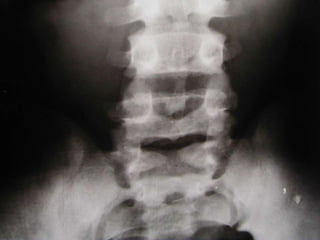

LUMBAR LATERAL

Estructuras Visualizadas

•Cuerpos Vertebrales T12-S1

•Espacios discales T12-L5

•FIV's

•PE's

•Facetas Articulares

•Pediculos

•Aorta Abdominal (cuando hay

ateroesclerosis)

LUMBAR LATERAL -

MARCADO